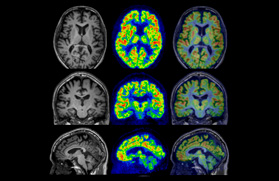

Fusion image of PET and MRI

Courtesy : Kindai University Hospital

- Imaging protocol

- Injected dose: 2.87 MBq/kg, 18F-FDG

- Uptake time: 42 minutes

- Scan time: 30 minutes